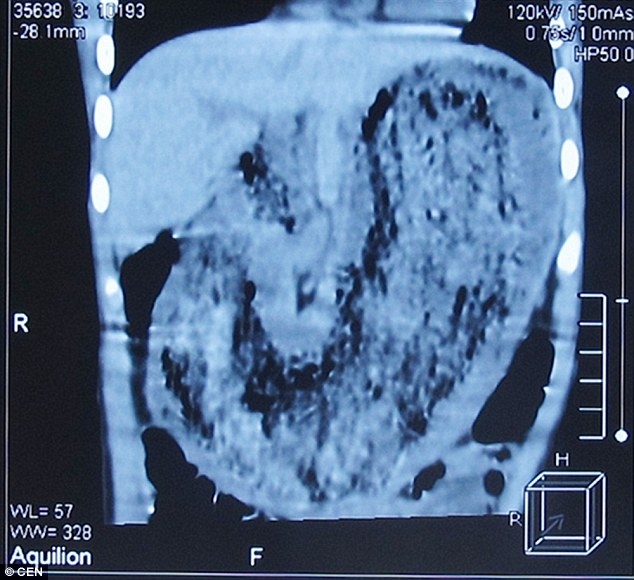

08 Ocak 2016 Cuma 12:00Annesi defalarca uyarmasına rağmen kız yapmaya devam etti. Bir süre sonra hastaneye kaldırılan genç kız ameliyat oldu